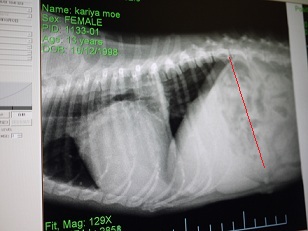

因みに赤い部分は肥大した左心室。

脊椎まで完全に食い込んだ状態。

こんな状態で、咳が出ない訳ないもんね・・(´Д`汗)

クッシングを持ってる割に、肝臓の肥大はなく、悪化すると

赤い軸が左に倒れてくるそうですが

軸がズレる様子もなく、状態はいいそうです。膵臓もOK。

肺水腫の兆候も画像からは無かった。